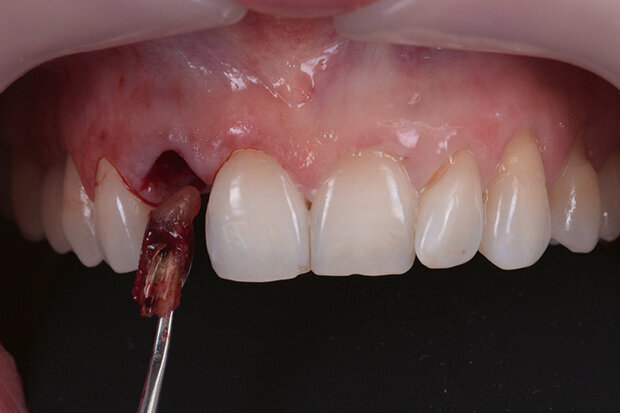

Fig. 9. Atraumatic tooth extraction

All the items required for the surgical intervention have been prepared and are now ready for use: This includes the printed drill template (Fig. 7) and the temporary implant restoration (Fig. 8). Tooth 12 is now extracted atraumatically in the “real world” (Fig. 9).